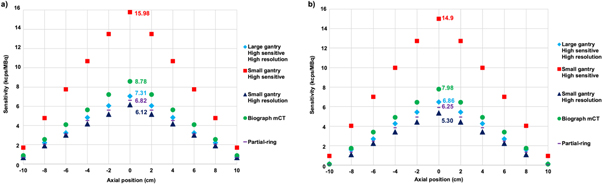

The estimated sensitivity for the different configurations at the center of the FOV and at 10 mm off-center are presented in figure 3. For all configurations, the sensitivity reaches its peak at the center of the FOV and starts to decrease towards the corners of the FOV. At the center of the FOV, the highest sensitivity (15.98 kcps MBq−1) was achieved by a small gantry and high-sensitivity detector, while the configuration with a small gantry and high-resolution had the smallest sensitivity (6.12 kcps MBq−1). The scanner equipped with high-sensitivity and high-resolution detectors has 16% sensitivity less than the Biograph mCT (7.31 versus 8.78 kcps MBq−1).

Figure 3. The calculated sensitivity along the z-axis at: (a) the CFOV and (b) 10 cm offset from the CFOV for all geometrical configurations including the Biograph mCT.